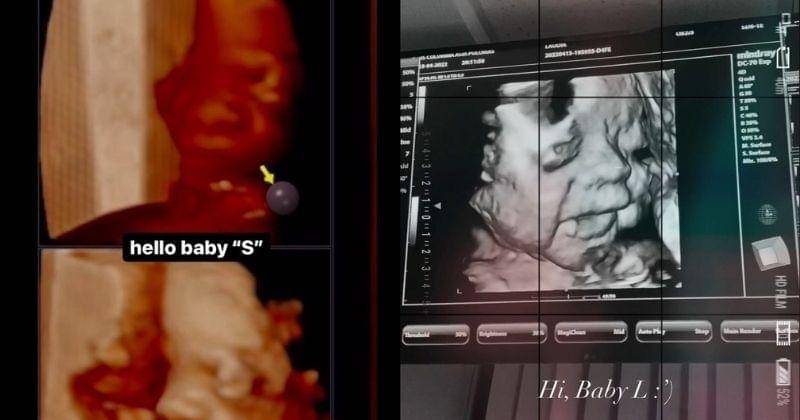

7. Dhea memanggil anaknya 'Baby S', sementara Laudia memanggil 'Baby L'

Hamil di waktu yang berdekatan, Dhea dan Laudia Ananda tampaknya sudah menyiapkan nama untuk bayi mereka. Di Instagramnya, Dhea memanggil si Jabang bayi dengan nama Baby S.

Sementara sang Adik, Laudia Ananda memanggil anak kedua dalam kandungannya dengan Baby L. Wah, kompak banget ya kakak-adik ini karena sudah sama-sama menyiapkan nama bayi mereka. Kira-kira jenis kelaminnya sama nggak ya?